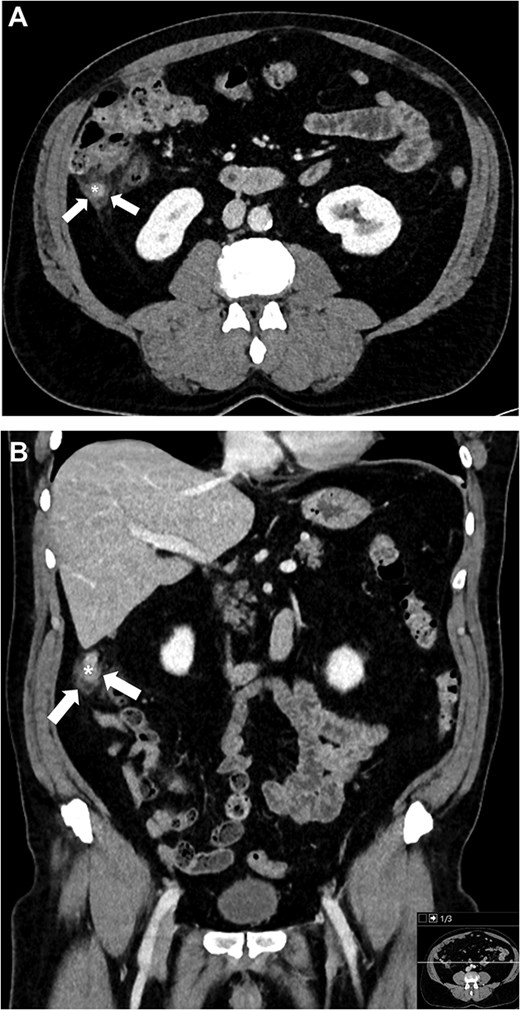

A man in his early 60s presented with a 2-week history of right lower quadrant abdominal pain, accompanied by low-grade fever. Laboratory tests showed a normal white blood cell count (8.2 × 109/L) and elevated CRP. Contrast-enhanced abdominal computed tomography (CT) confirmed uncomplicated acute appendicitis with focal thickening at the appendiceal tip (maximum diameter ~11 mm) and periappendiceal fat stranding (Fig. 1). There was no abscess, perforation, appendicolith, or mass, and the cecum appeared unremarkable.

Contrast-enhanced CT images of the abdomen at the initial presentation, demonstrating an inflamed appendix with focal thickening at the appendiceal tip (*) and periappendiceal fat stranding (arrows) on axial (A) and coronal (B) planes.